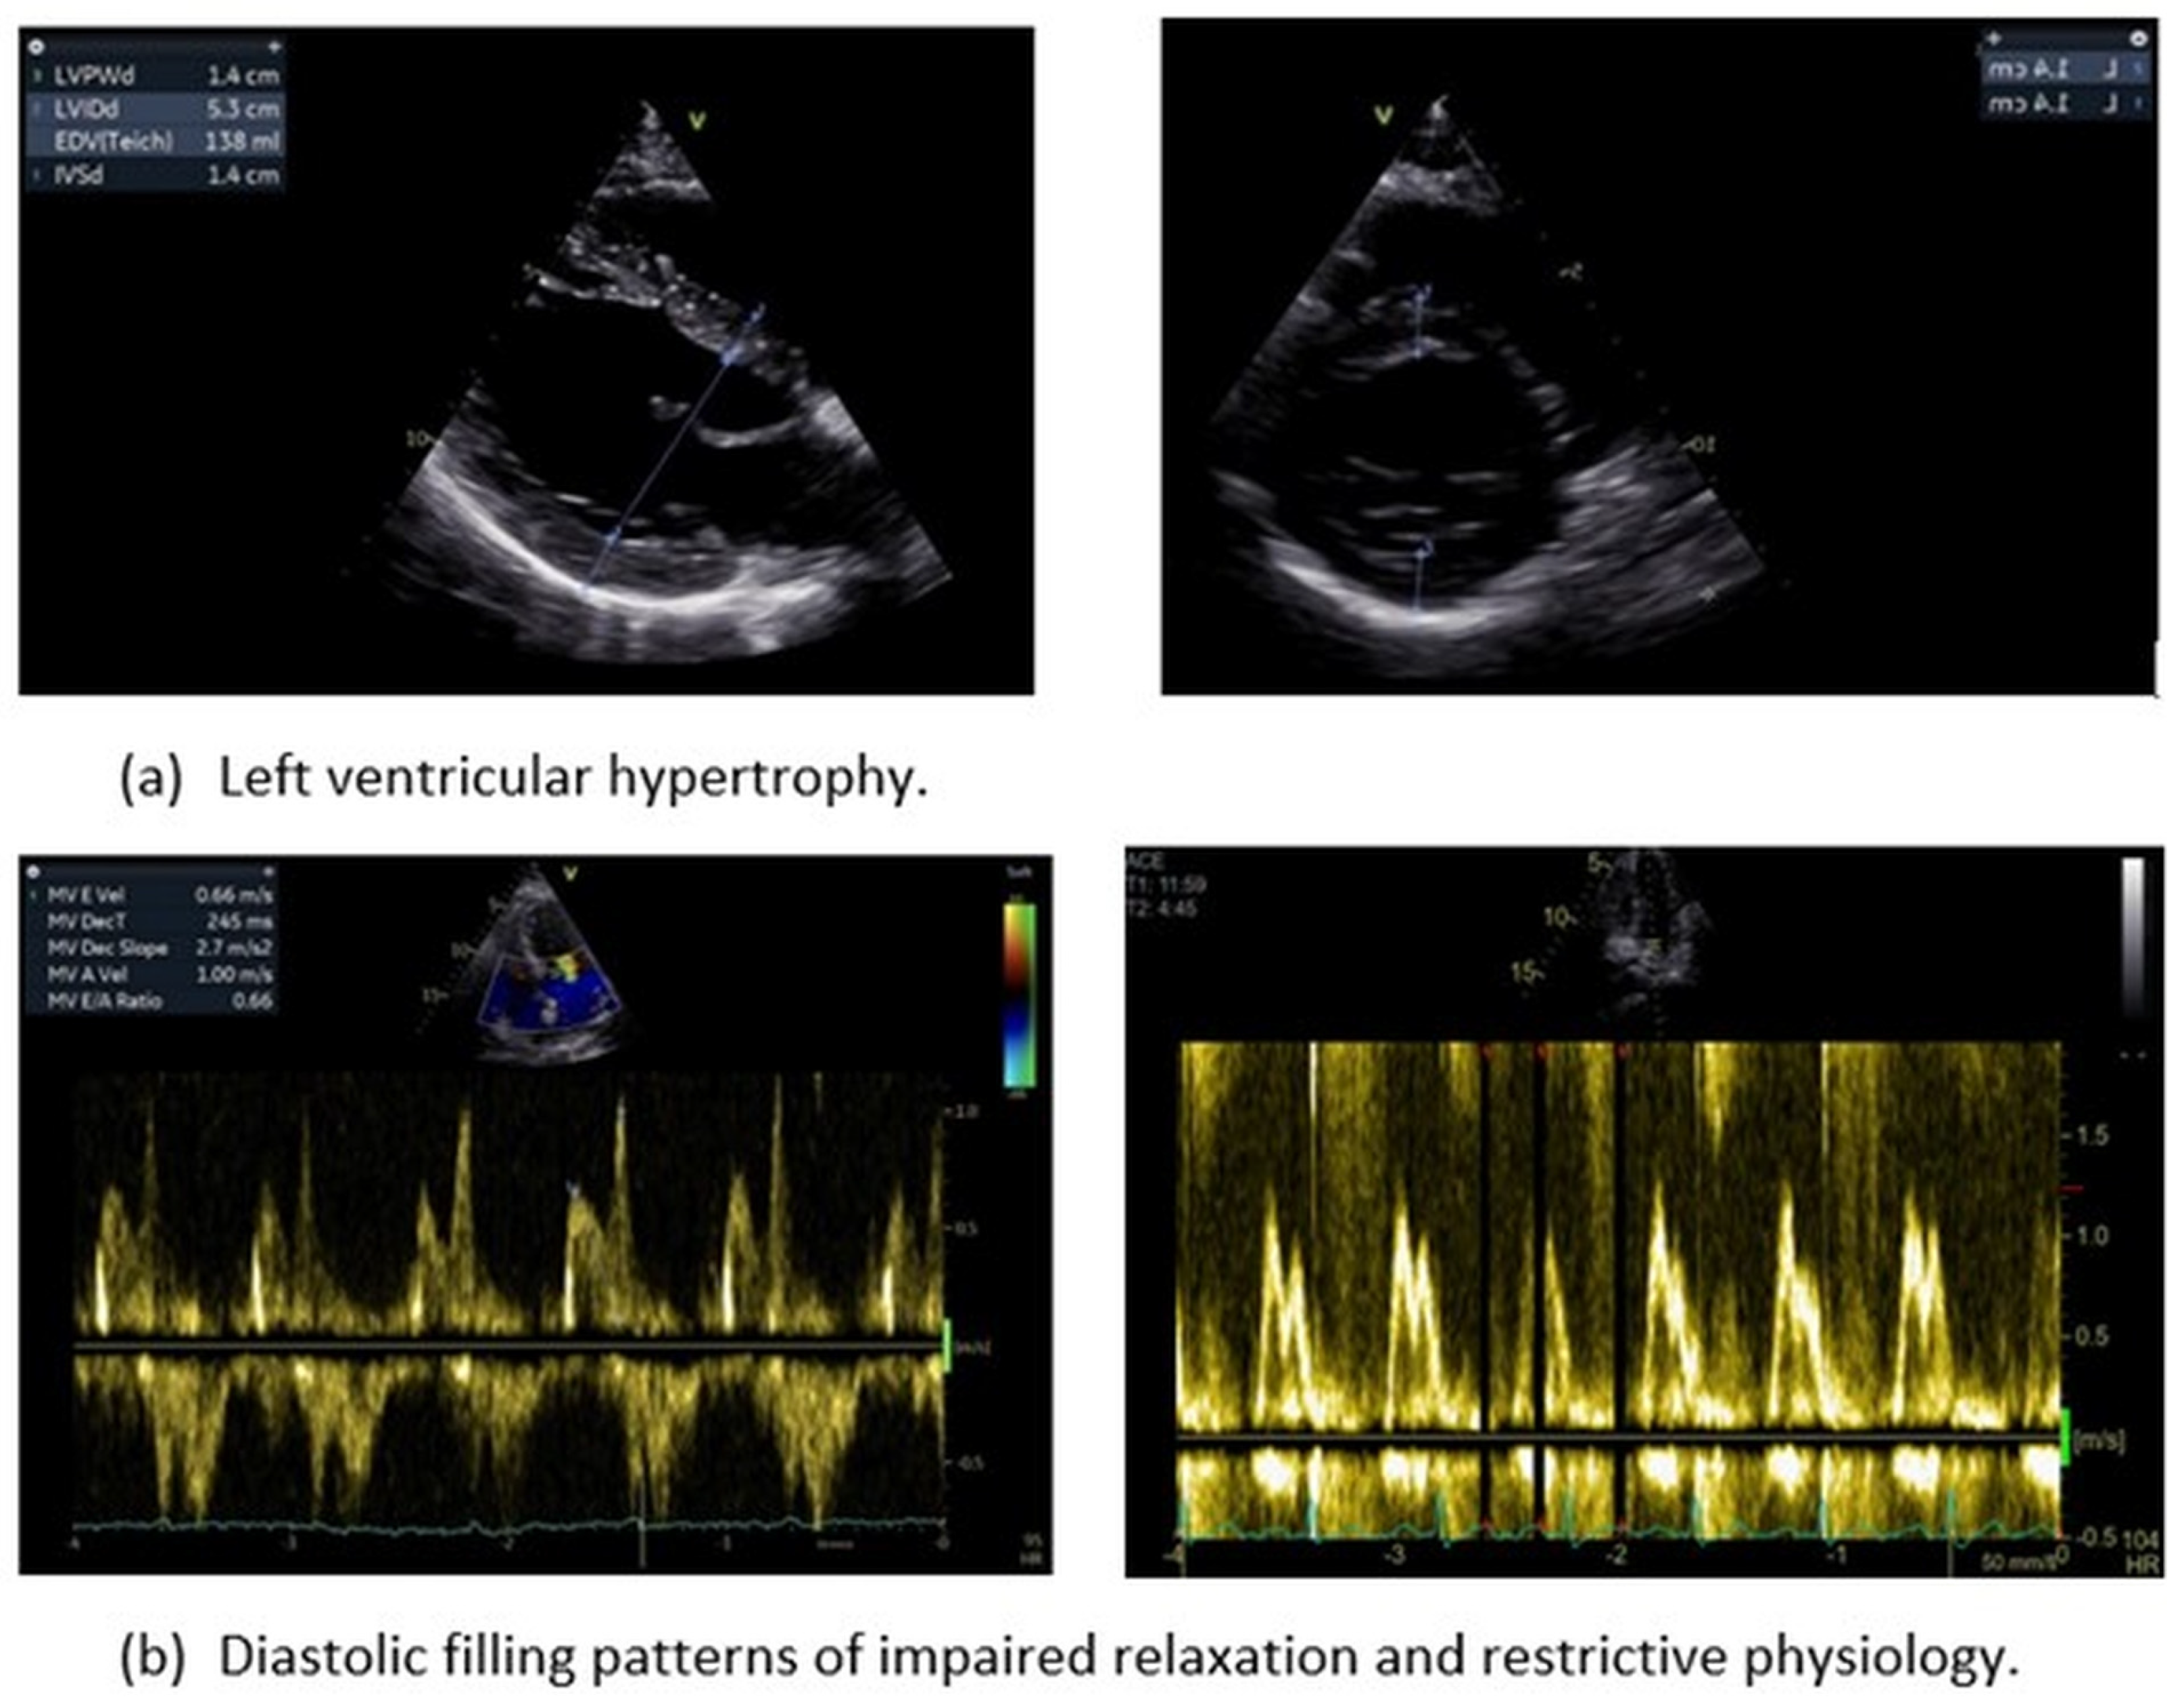

3.1. Left Ventricular Hypertrophy